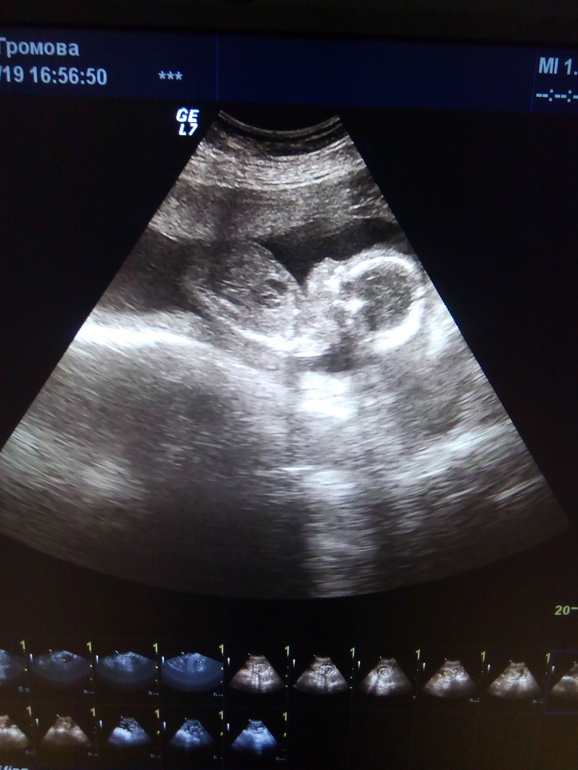

Пол малышаДевочки роднинькие хочу сказать большое спасибо за теплую поддержку, за Ваши розовенький апчихи. Я пока ещё в шоке и до конца не верю, что у нас будет доченька. То самое чувство когда сбывается самая большая мечта.....Я с первых дней чувствовала но думала со мной такое не может случится. Моя стесняшка на УЗИ закрывала личико ладошками и вертела попой- истинная леди.